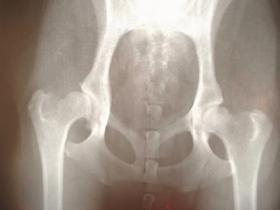

膝に水が溜まる原理

膝に水が溜まる原理を理解するためには膝の構造から理解する必要があります。

水が溜まる関節は、膝の人がほとんどです。膝の関節には通常、2〜4mlの滑液が含まれています。

膝は、大腿骨、膝蓋骨、脛骨の3つの骨で構成されており、3つの骨の間に関節包というクッションの役割を果たす袋があります。この中に滑液という水が詰まっていてクッションの役割を果たしています。滑液は関節の潤滑や衝撃収取の役割を果たしており、関節包の内側を覆う滑膜で産生されています。